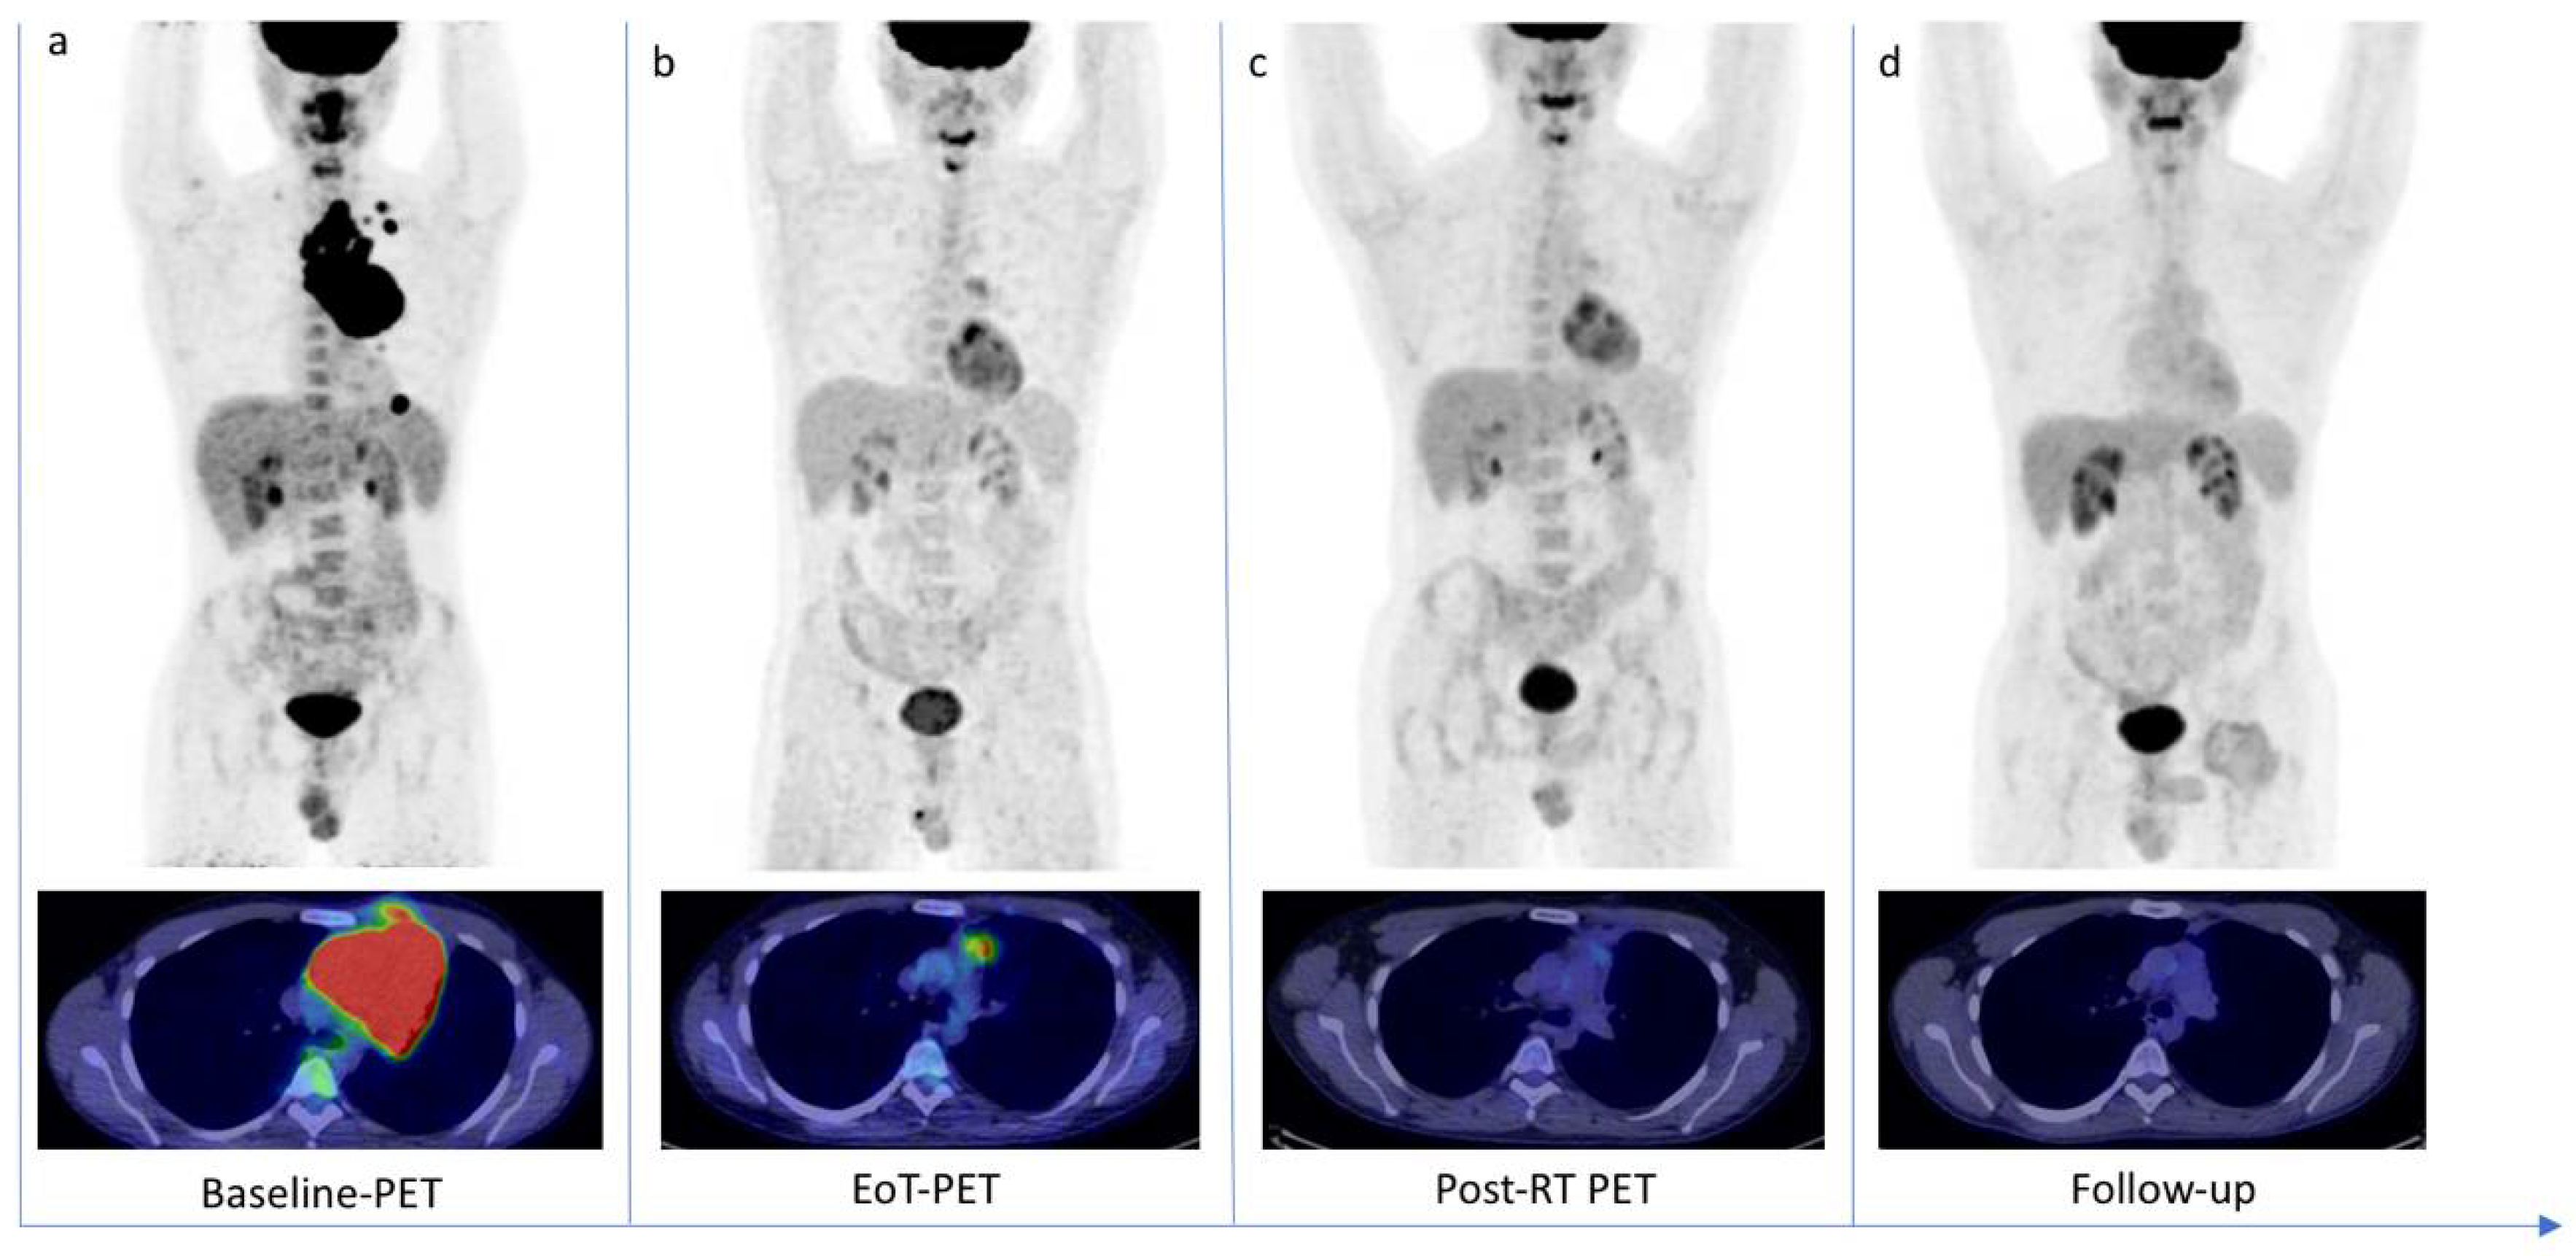

![[⁶⁸Ga]Ga-tilmanocept PET/CT lymphoscintigraphic images of the same ...](https://www.researchgate.net/publication/357378954/figure/fig5/AS:1146753294303239@1650418699819/a-c-Hotspot-on-99mTcTc-tilmanocept-SPECT-CT-asterisk-d-f-consisting-of-multiple_Q640.jpg)